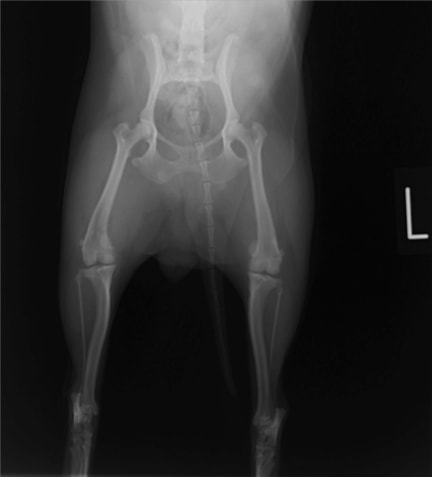

■ 症例24 キャバリア 7か月

左右膝蓋骨内方脱臼(左:グレードⅣ 右:グレードⅢ)

以前から左右後肢の跛行が認められ、整形外科学的検査・レントゲン検査により左右の膝蓋骨脱臼が認められた。症状が重度である左膝の膝蓋骨脱臼整復術を行った。外科手技は縫工筋及び内側広筋の解放、脛骨粗面の外側転位、滑車ブロック形造溝術、内外側関節方の縫縮を実施した。術後一か月時点で、左の膝蓋骨は安定しており経過は良好である。

本症例は成長期における重度の膝蓋骨脱臼であり、術後の再発の可能性もあるため、経過をしっかりと観察していく必要がある。また、今回手術を実施していない右膝に関しても経過を観察し、手術を検討していくこととする。